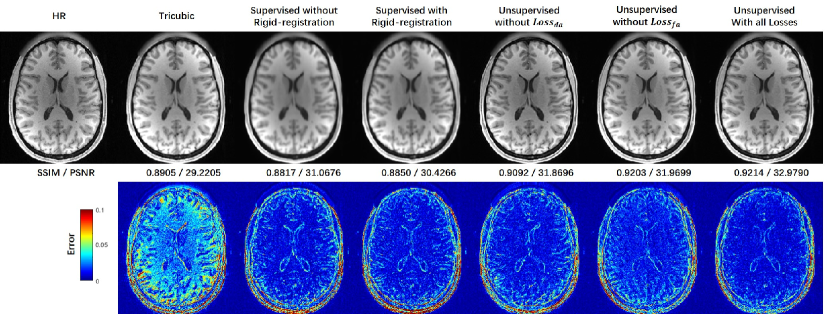

Table 1: Quantitative results of ablation study for MRI SRR with misaligned LR and HR images of the HCP dataset and scale factor of 2×2×22222\times 2\times 2.

Supervised without Supervised with Unsupervised with Unsupervised with Unsupervised with

Rigid-Registration Rigid-Registration DA in Feature Space DA in Image Space DA in Both Spaces

SSIM 0.8939±0.0140plus-or-minus0.89390.01400.8939\pm 0.0140 0.9025±0.0116plus-or-minus0.90250.01160.9025\pm 0.0116 0.9162±0.0104plus-or-minus0.91620.01040.9162\pm 0.0104 0.9229±0.0093plus-or-minus0.92290.00930.9229\pm 0.0093 0.9247±0.0097plus-or-minus0.92470.0097\mathbf{0.9247\pm 0.0097}

PSNR 32.7886±1.5546plus-or-minus32.78861.554632.7886\pm 1.5546 32.7823±1.5013plus-or-minus32.78231.501332.7823\pm 1.5013 33.5224±1.6849plus-or-minus33.52241.684933.5224\pm 1.6849 33.5642±1.7719plus-or-minus33.56421.771933.5642\pm 1.7719 34.2729±1.8080plus-or-minus34.27291.8080\mathbf{34.2729\pm 1.8080}

We evaluated our network in various configurations on the same task of SRR for misaligned LR and HR datasets to find the best performance. The effect of DA in the image space and latent feature space was evaluated. Besides, we compared our network to the same backbone network trained in the supervised strategy with the misaligned training data to reveal the effect of the degradation-learning modules. As shown in Table 1, all the configurations of the UDEAN outperformed the supervised learning using the same generator by over 0.014/0.74 dB in SSIM/PSNR using misaligned LR and HR image from the HCP dataset with the scale factor of 2×2×22222\times 2\times 2. Among the configurations of the UDEAN, the performance was downgraded by 0.009/0.75 dB or 0.002/0.71 dB in SSIM/PSNR when DA in only latent feature space or image space was applied, respectively.

Furthermore, Fig. 5 shows the visual effect of the reconstructed SR images and the error maps to the HR images. The SR image reconstructed by the supervised methods were highly blurry either with or without rigid image registration. On the contrary, the quality of SR images reconstructed by the UDEAN was significantly improved even with DA only in latent feature space or image space. The errors of the reconstructed anatomical structures were further reduced when DA in both domains was applied in the training process.